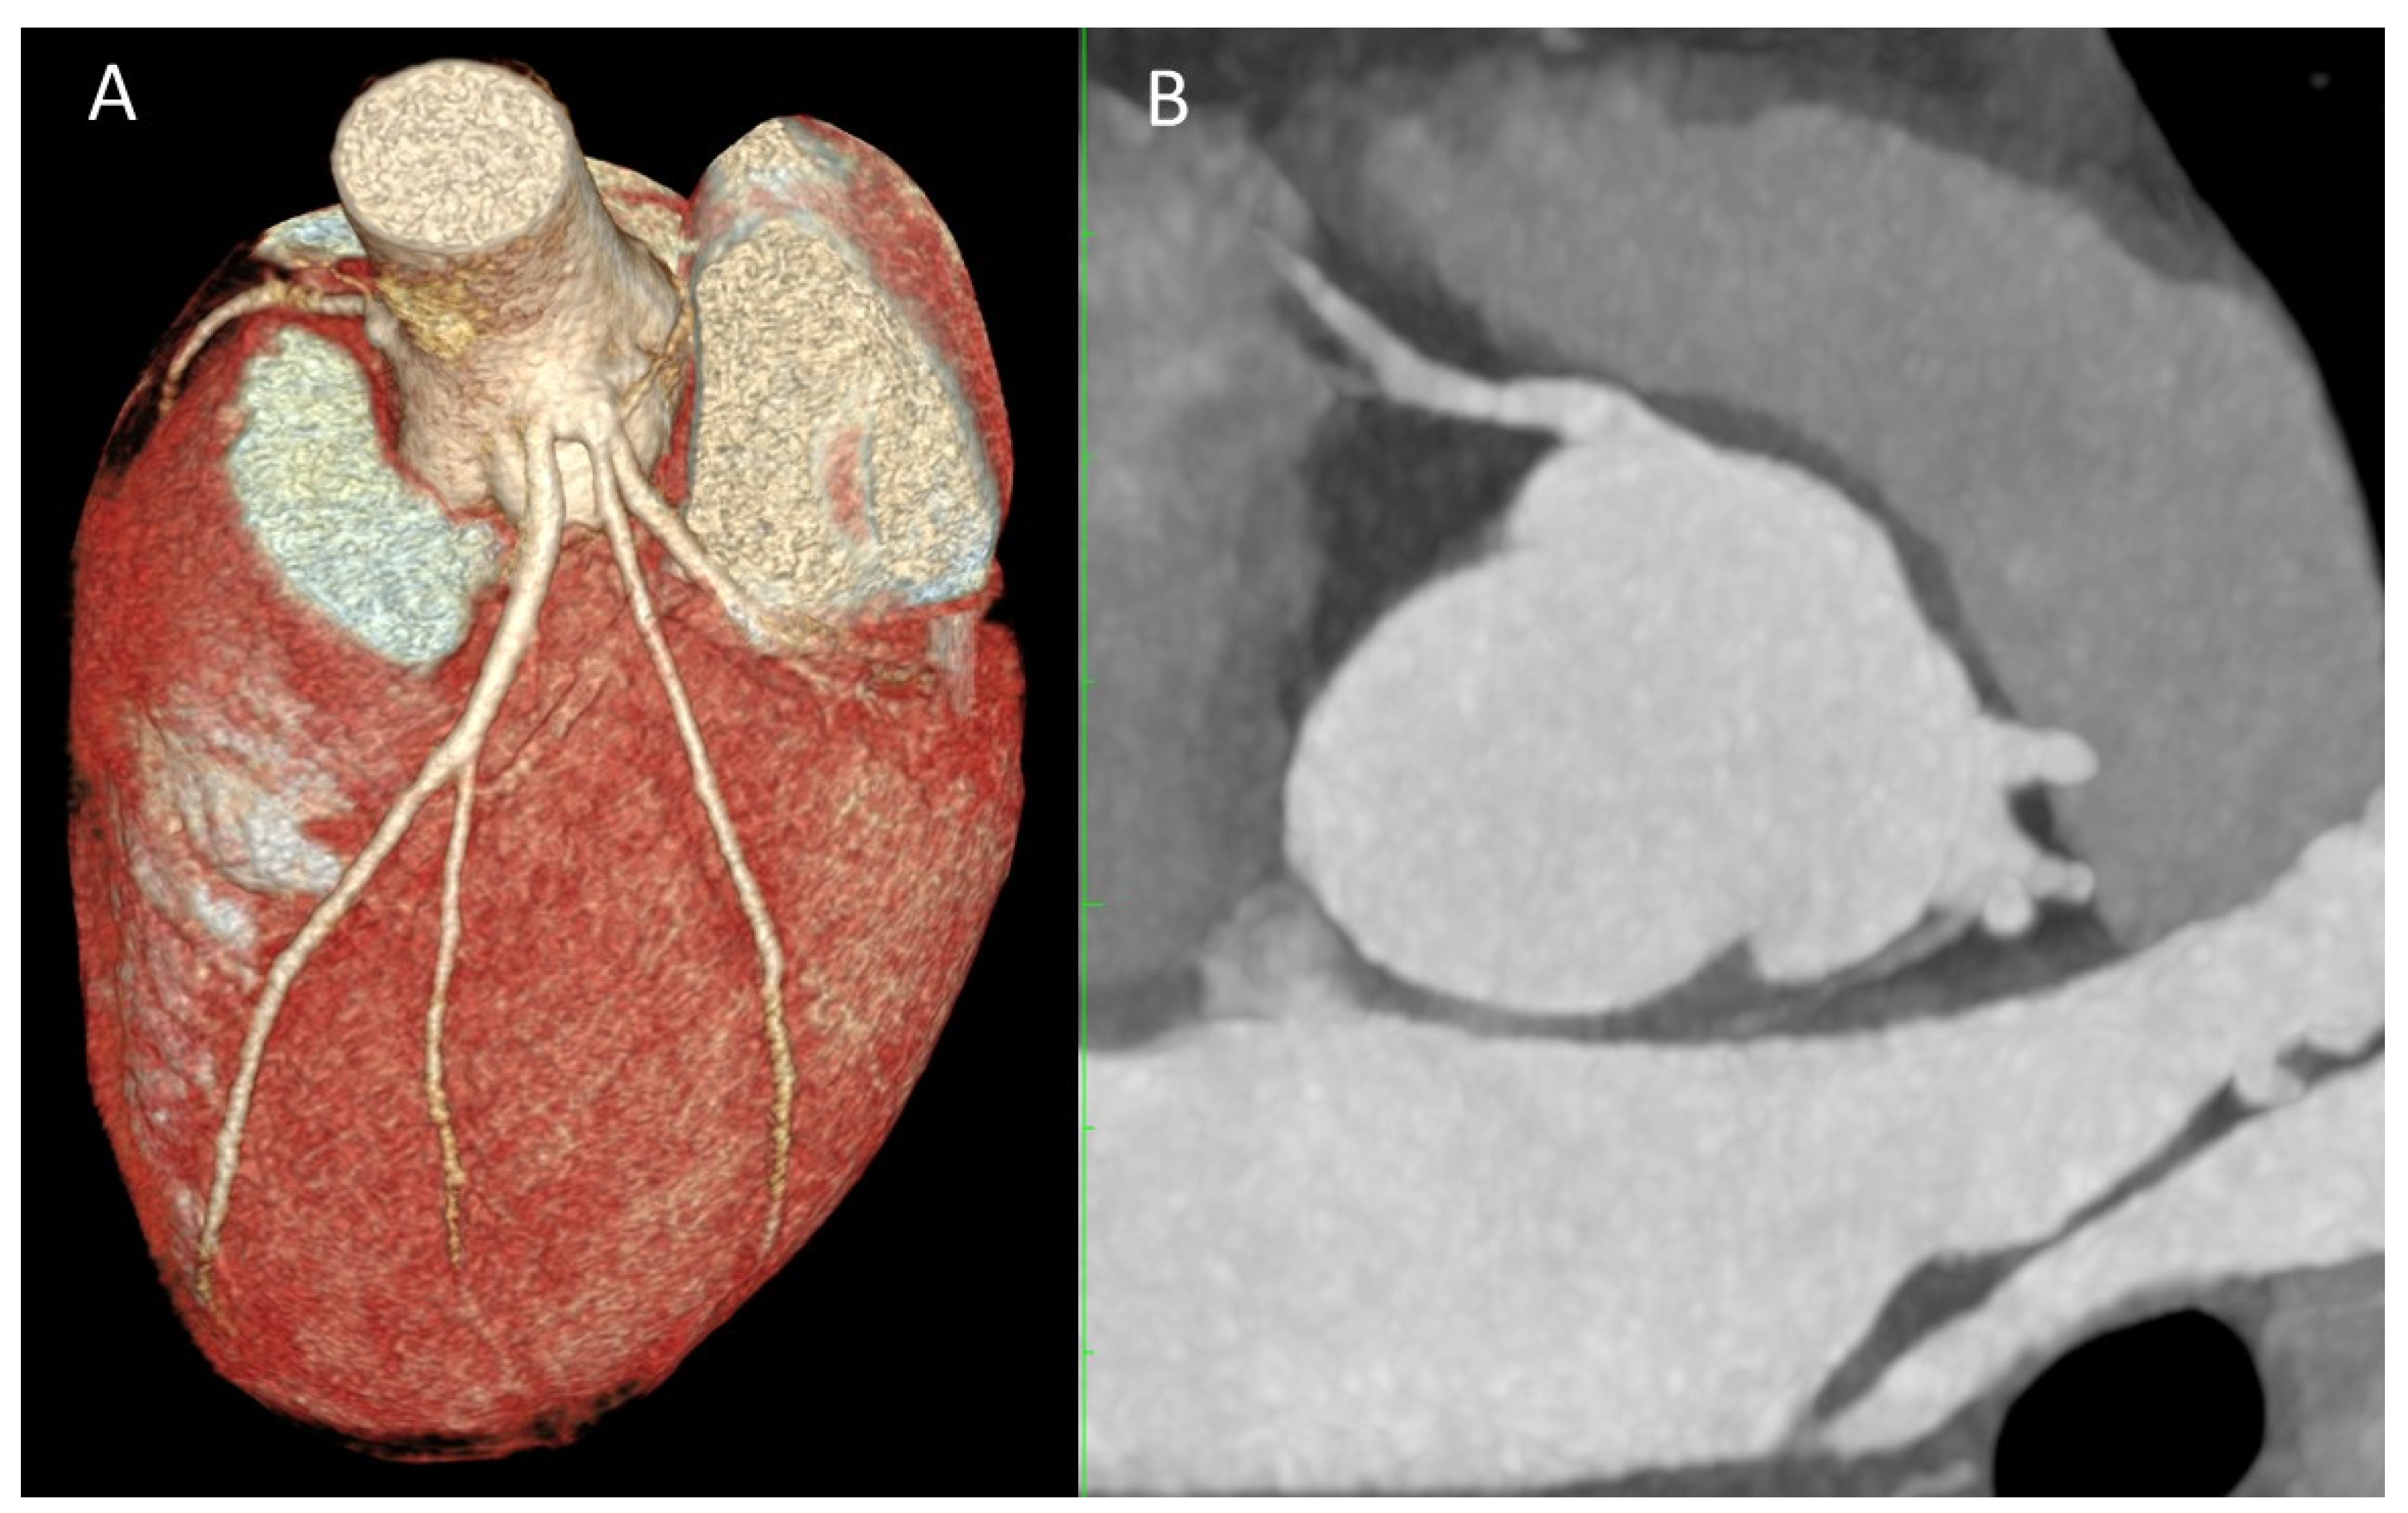

Figure 5. Anomalies of aortic origin: (A) Three-dimensional projection of the right right coronary artery arising from the left sinus of Valsalva (B) CCTA image of an anomalous aortic origin of the right coronary artery from the left sinus of Valsalva (AAORCA).

AAORCA is more common (0.03%–0.92%) than AAOLCA (0.03%), but AAOLCA is more clinically significant (Figure 4 and Figure 5). While both anomalies are linked to sudden cardiac death (SCD), a study analyzing 1,866 cases of SCD among American athletes found that 17% were due to coronary anomalies, with AAOLCA being the most frequently implicated. Therefore, both anomalies can be classified as class III Rigatelli. ACAOS can be further categorized depending on the course of the anomalous coronary artery, which will drastically change de prognosis of these anomalies: interarterial, pre-pulmonic, subpulmonic (transseptal), retroaortic and retrocardiac (Figure 5). The interarterial course is most frequently associated with high-risk features of ischemia and SCD due to several anatomical and physiological factors. These include an acute-angled takeoff from the aorta, a slit-like lumen, both of which can limit blood flow and an intramural course (the coronary artery runs through the aortic wall, sharing the tunica media with the aorta), which makes the artery prone to compression, particularly during systole (Figure 6). While the exact pathophysiological mechanisms underlying ACAOS are not yet fully understood, all clinical manifestations—angina, arrhythmias, dyspnea, syncope and SCD, ultimately result from a limited coronary reserve (2,3,5,13,14,19,22,23).